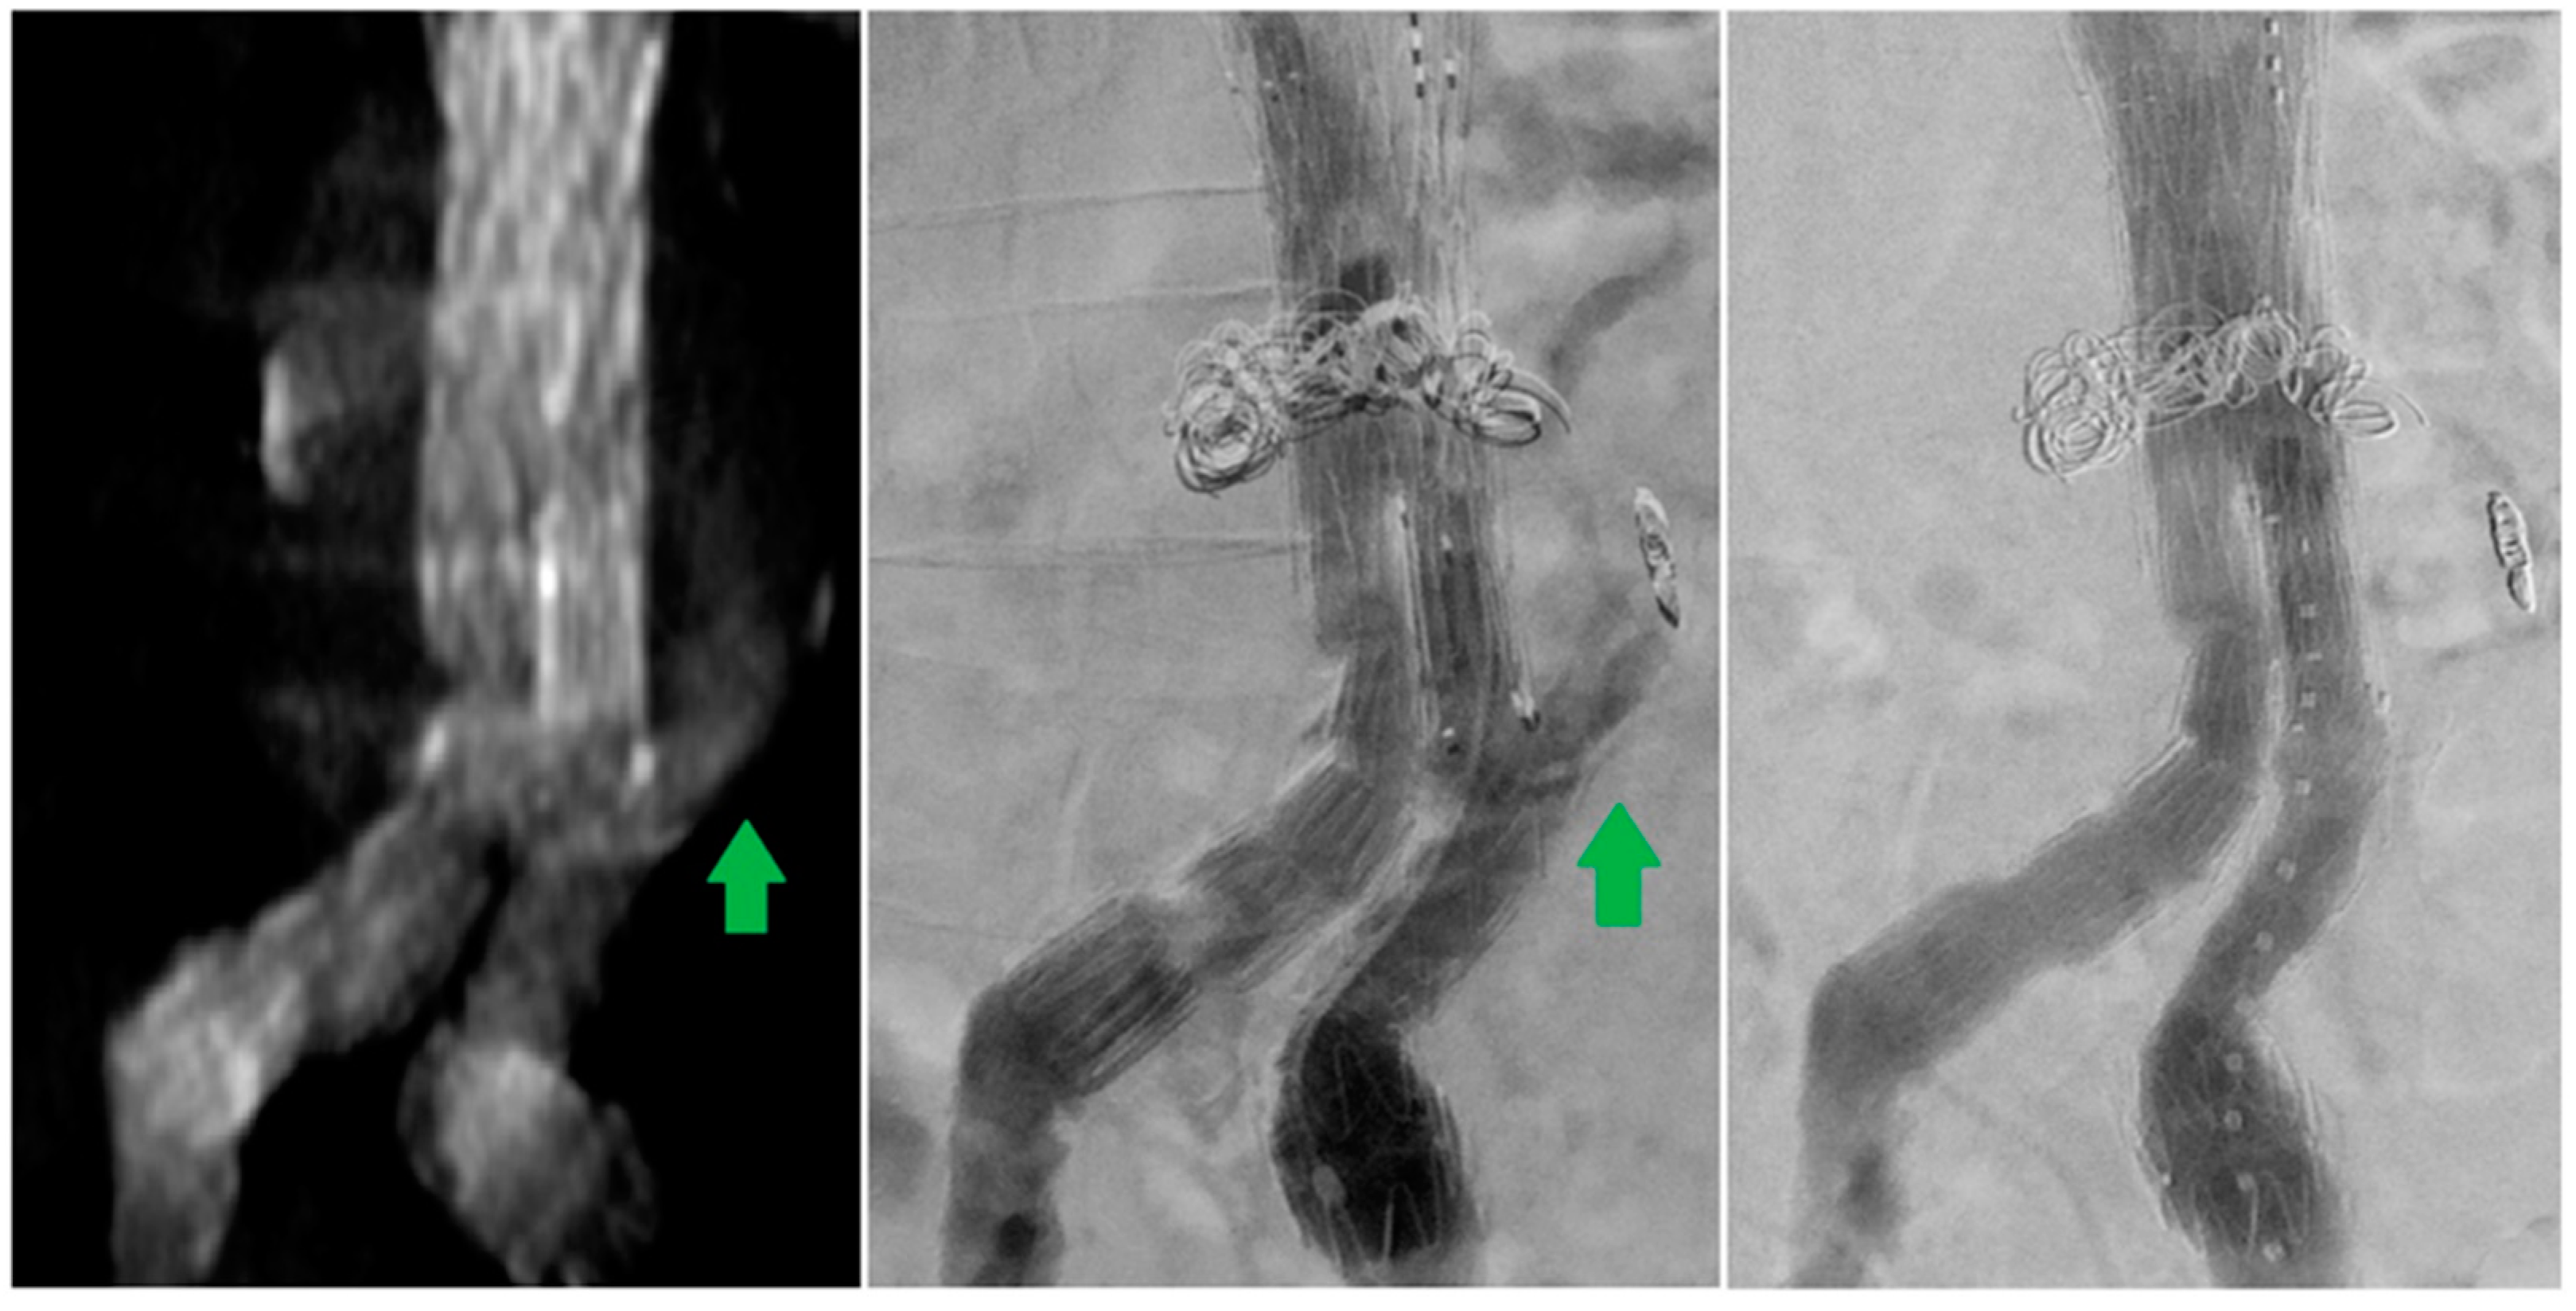

From www.semanticscholar.org

Figure 2 from Type II Endoleak Following Endovascular Repair of Radiopaedia Endoleak of these complications, endoleak is the most notable and poses the greatest risk of potential future aortic. endoleaks occur when an aneurysmal sac continues to be pressurised despite endoluminal stent placement. type ii endoleaks, can potentially enlarge and pressurize the aneurysm sac with a risk of rupture. endoleak is due to incomplete sealing or exclusion of. Radiopaedia Endoleak.